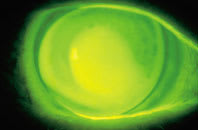

| Figure 2. A traditional RGP lens with excellent mid-peripheral alignment. | Figure 3. The reverse geometry lens on the patient's right eye. |

Step 3. Determine the reverse curve radius. The ultimate goal is a lens that significantly reduces the amount of apical clearance, yet provides mid-peripheral alignment for optimum lens centration, movement and comfort (Figure 3). The reverse curve joins the central base curve radius with the alignment curve radius (Figure 4). The laboratory or practitioner can make this calculation by incorporating sagittal height calculations into any number of software programs. In our case, the software indicated that a reverse curve radius of 6.58mm (51.25 diopters), would join two previously established radii.